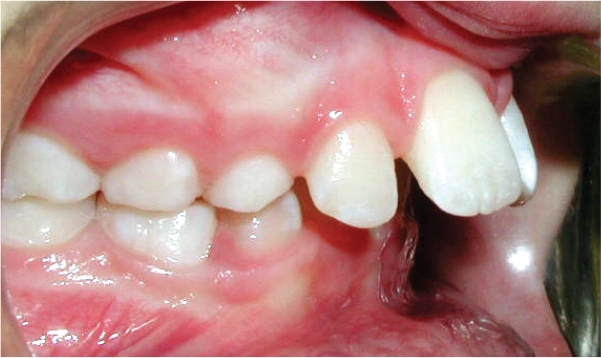

Ectopic Eruption

Ectopically erupting maxillary molar